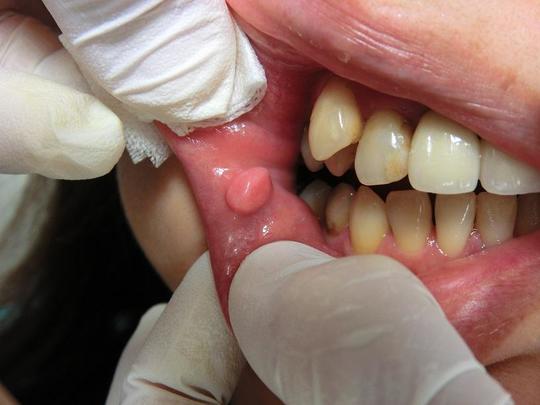

口腔内のイボ・できもの(線維腫・乳頭腫などの良性腫瘍)をCO2レーザー(炭酸ガスレーザー)で切除した症例。

線維腫、乳頭腫などは誤って粘膜を噛んでしまうと出現することが多く、またその部位を繰り返し噛んでしまい大きくなるケースもあります。

口唇の場合

術前

頬粘膜(口唇に近い頬粘膜)の場合

直径約10mm